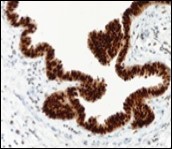

Figure 11.Cutaneous ciliated cyst with immune reactivity to cyto-keratin (19).

Immune Histochemical Elucidation

Epithelium of cutaneous ciliated cyst is immune reactive for pan cytokeratin (CKae1/ae3) antigens, epithelial membrane antigen (EMA), oestrogen receptors (ER), progesterone receptors (PR), Wilm’s tumour protein (WT-1) and paired box gene 8 (PAX8). Immune non reactivity is cogitated for S100, smooth muscle actin (SMA), carcino-embryonic antigen (CEA), desmin, thyroid transcription factor(TTF1), p63 and glial fibrillary acidic protein (GFAP).

Smooth muscle actin (SMA) is immune non reactive, thereby suggesting an absence of smooth muscle within the cyst wall. Intense immune reactivity can be cogitated within epithelial nuclei for oestrogen receptors (ER) and progesterone receptors (PR). Aforesaid immune reactions are indicative of Mullerian origin of cutaneous ciliated cyst.

Focal epithelial staining for periodic acid Schiff’s(PAS) stain is enunciated 4, 5. Pan cytokeratin (CKae1/ae3) are diffusely immune reactive.